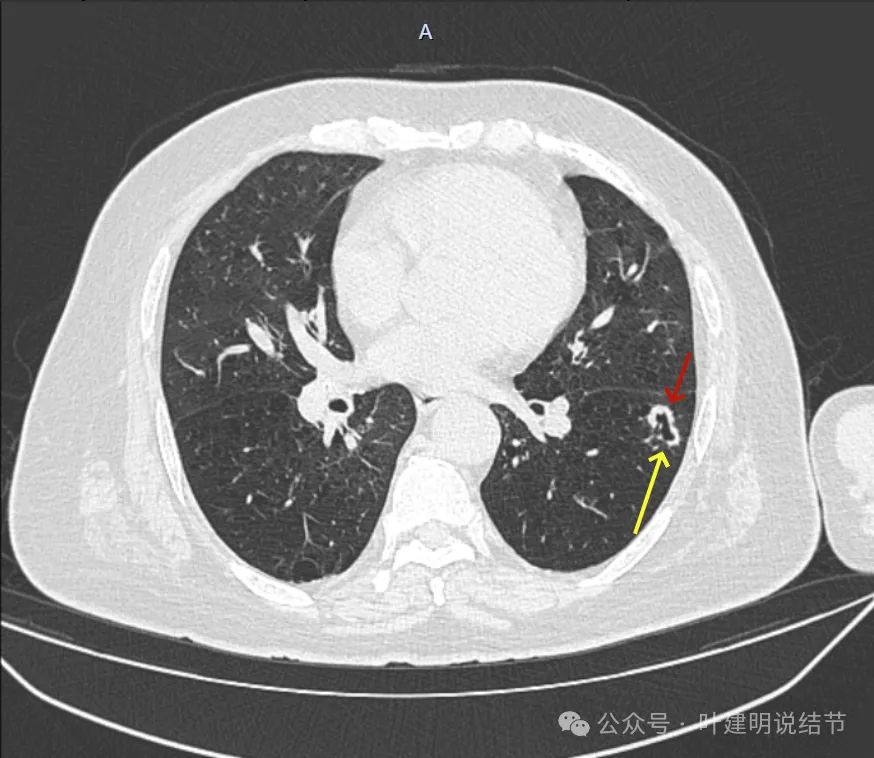

冠状位见病灶基本实性,小血管进入明显,囊壁厚薄不均,囊腔内壁不光滑,表面浅分叶。

矢状位显示较强的收缩力的样子,表面明显棘突的样子,而且囊壁密度杂乱,伴浅分叶征以及胸膜牵拉征。

前后最明显层面对比:

间隔才三个月,明显感觉更不舒服,更像恶性了些。